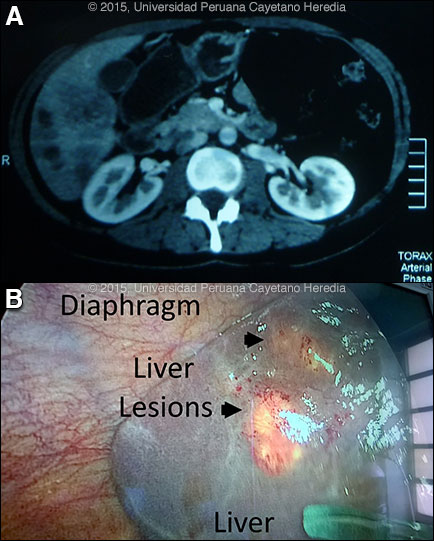

Epidemiology: Physician, born on the coast of Perú but living for many years in the suburbs of Cusco with occasional exposure to farm animals. Non-smoker, no alcohol abuse, no known TB exposures. No HIV risk factors. Normal diet without ingestion of undercooked or unusual foods. Physical Examination: Afebrile with normal vital signs. Unexceptional physical examination except for mild tenderness to palpation in the right upper quadrant of the abdomen and a palpable liver. Laboratory Examination: Altitude adjusted hemoglobin 9.9 g/dL. WBC: 12,300 with 67% eosinophils, Platelets: 387,000. AST: 38 U/L (N), ALT: 28 U/L (N). Alkaline phosphatase: 236 U/L (N<104). Total bilirubin: 1.2 mg/dL. HBsAg: Negative. HCV ab: Negative. Stool O & P negative X3. CT of the liver showed several hypodense lesions in the liver parenchyma [Image A]. The patient underwent laparascopic liver biopsy for suspected metastatic liver lesions [Image B].

![]() Discussion: IgG Fas2 ELISA [Trans R Soc Trop Med Hyg. 1999 Jan-Feb;93(1):54-7] was positive for Fasciola hepatica at the UPCH–UTMB (University of Texas Medical Branch Galveston) Collaborative Research Center in Cusco. This test is more specific than Western blot or Arc2 immunodiffusion. An ELISA performed 1 month earlier was negative. The liver biopsy showed eosinophilic granulomas [Image C]. A F. hepatica larva from another patient with acute infection from our case files is shown in Image D. Fasciola hepatica is a trematode (fluke or flatworm) in which the mature adult parasites inhabit the large biliary ducts. As with all other trematodes, Fasciola hepatica requires a snail intermediate host. Eggs produced by the hermaphroditic adults pass with the feces and hatch, releasing larvae in fresh water. After passing through a snail, mature cercariae emerge and rapidly encyst on various kinds of aquatic vegetation such as watercress or alfalfa. Recent data, however, also suggests waterborne transmission. Our patient denies ingestion of watercress or alfalfa, but did admit to eating salads with lettuce. After ingestion by a human or animal definitive host, the metacercariae excyst in the duodenum and larvae penetrate the intestinal wall and subsequently migrate directly into the liver via Glisson’s capsule and embark on a destructive migratory process through the hepatic parenchyma for 3 to 4 months until they reach large biliary ducts, where they then mature to adults. The mature adults are from 1 to 3 cm long and attach to the biliary epithelium by a single ventral sucker. In the absence of direct visualization of adults, characteristic eggs can be seen on stool examination, but more often patients present in the early migratory phases of infection prior to maturation of the worm and the onset of egg-laying. Specific serology is the test of choice. The distribution of F. hepatica is cosmopolitan, but is by far the most common in cattle-raising areas where herbivores are common definitive hosts. Other important definitive hosts are goats, sheep, horses, llamas, vicunas, and camels. The contiguous Altiplano regions of the Peruvian and Bolivian Andes are highly endemic, with human prevalence rates as high as 67% in some villages. In the agricultural areas near Cusco, the prevalence in children 3 to 12 years old is 11% by stool microscopy and Fas2 ELISA [Am J Trop Med Hyg. 2014 Nov;91(5):989-93]. Egypt, Cuba, and Northern Iran are also highly endemic and the parasite is emerging in Vietnam and Cambodia. Cooking, which would kill the metacercariae, dramatically changes the flavor of watercress and the population is reluctant to adopt this simple measure. Emoliente, a local tea-like drink that uses drops of watercress juice to provide a bitter flavor is a frequent vehicle of infection. Clinically, the disease can be divided into acute and chronic phases. During the acute phase, migrating parenchymal larvae generally cause fever, eosinophilia, right upper quadrant pain and especially significant anorexia. Vomiting and weight loss of 20 kg or more may develop, which usually abates when the larvae mature to adults. The adult flukes in the biliary tree are generally asymptomatic but some patients develop chronic manifestations including right upper quadrant pain, nausea, vomiting, and hepatomegaly. Eosinophilia and abnormal liver function may develop but are less common than with acute disease. Adult flukes may cause hyperplasia, desquamation, thickening, and dilatation of the bile ducts. Malignant degeneration and cholangiocarcinoma such as results from chronic infection with the oriental liver fluke Clonorchis sinensis has not been reported with F. hepatica. We have reported a case series with clinical findings and evolution of disease [Am J Trop Med Hyg. 2008 Feb;78(2):222-7]. Please see Gorgas Case 2005-02 for a CT image of another example with the typical larval tracks seen in acute disease. The differential diagnosis of eosinophilia with accompanying destructive hepatic lesions is limited. Toxocariasis causes hypereosinophilia with hepatomegaly but the pathology results from small granulomas around individual non-migrating larvae and not the large destructive lesions seen in our patient. Eosinophilia is common in Perú, so it may be due to an unrelated event present concomitantly with a bacterial liver abscess; this had been the initial impression in this case. Fasciola hepatica is the only trematode infection for which praziquantel is not the drug of choice. The WHO has put the anthelmintic triclabendazole (Egaten, Novartis) on its essential drugs list. Egaten is registered in Perú (as in Mexico and Egypt) and is available via free donation from the WHO. In the U.S. the drug is available from the CDC Parasitic Drug Service. The usual dosage is 10 mg/kg with a meal. Many practitioners repeat the dosage 12 to 24 hours later. In intial studies at our institute the cure rate was 96%, but it has been lower in recent experience. Treatment with triclabendazole 10 mg/kg in a single dose was provided to the patient with resolution of her symptoms within one week. On follow up 6 weeks after treatment, she has recovered her appetite and energy level and her altitude adjusted hemoglobin level is 11.4 g/dL.